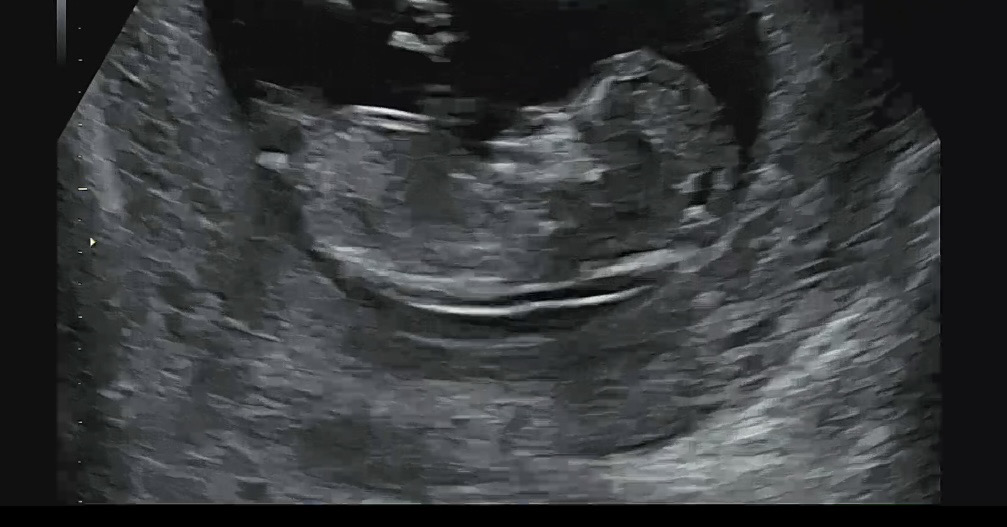

12주 각도법 봐주세요!!